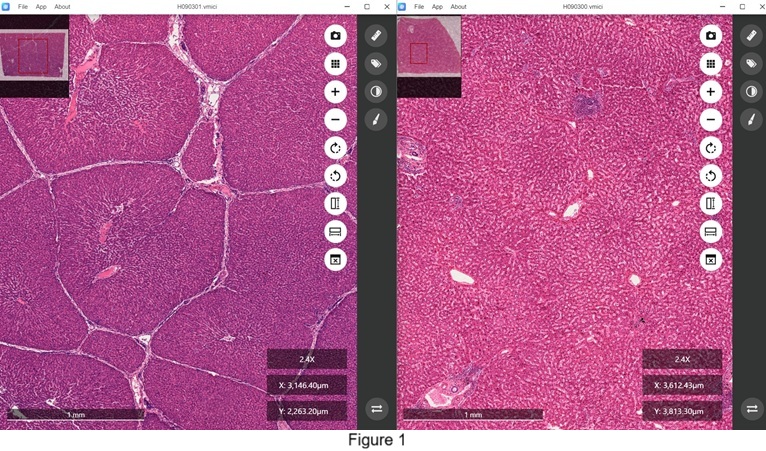

It now allows users to open various image data files in separate windows, enabling independent operation. This enhancement facilitates the concurrent observation and comparison of tissue structures across multiple microscopic sections. One significant application is the comparison of structural differences between human liver and swine liver. As illustrated in Figure 1, the human liver lacks distinct boundaries between hepatic lobules (right), whereas the swine liver is characterized by clearly defined hepatic lobules (left).